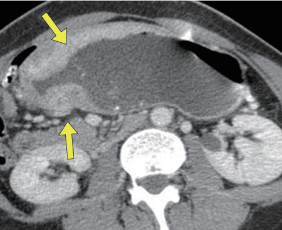

간은 인체에서 가장 큰 장기 중 하나로, 여러 가지 중요한 기능을 수행합니다. 간 질환은 매우 일반적인 문제로, 신속하고 정확한 진단이 필요합니다. 복부 CT를 통해 간의 경화, 종양, 지방간 등 다양한 문제를 확인할 수 있습니다. 특히 간암의 경우, CT 촬영은 초기 단계에서 종양의 크기와 위치를 평가하는 데 중요한 역할을 합니다. CT 이미지는 간 내 혈관과 주변 조직의 상태를 상세히 보여주기 때문에, 간암이 다른 장기로 전이되었는지 파악하는 데도 유용합니다.

간암은 조기 증상이 거의 없기 때문에 진단이 늦어지는 경우가 많습니다. 그러나 복부 CT를 통해 초기 증상을 발견할 수 있다면, 치료 옵션이 훨씬 다양해집니다. 간암의 원인으로는 간염 바이러스 감염, 알코올 남용, 비만 등이 있으며, 이들 요인을 관리함으로써 예방할 수 있습니다. CT 촬영을 통해 조기에 간암을 발견하면, 간 절제술이나 간 이식과 같은 치료를 통해 생존율을 높일 수 있습니다.